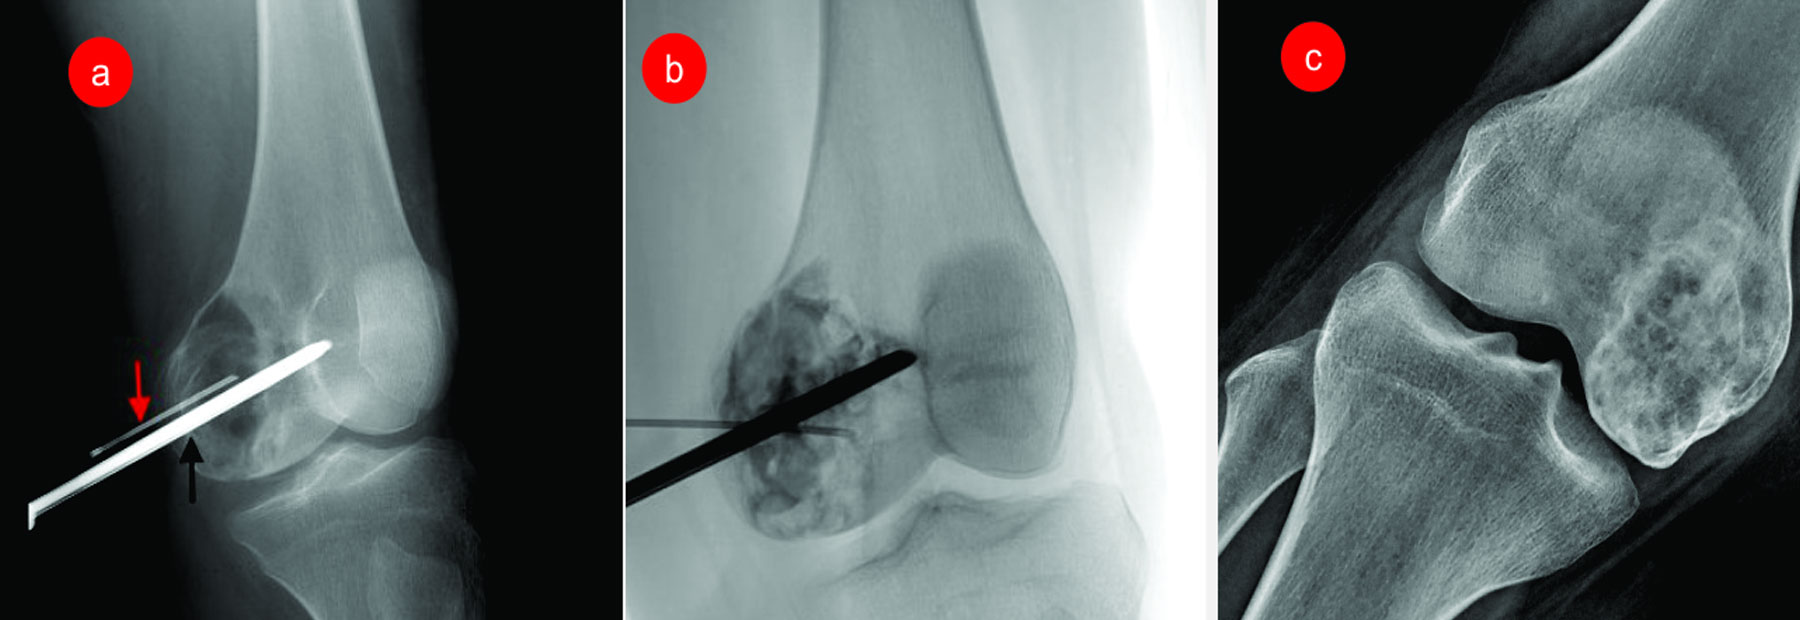

Limb Reconstruction surgeries- Removal of complete tumours with no remaining disease...

Bone tumours presented with abnormal swelling and pain at limbs, joints and back of trunk...